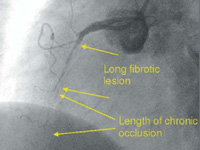

Before implantation |

After implantation |